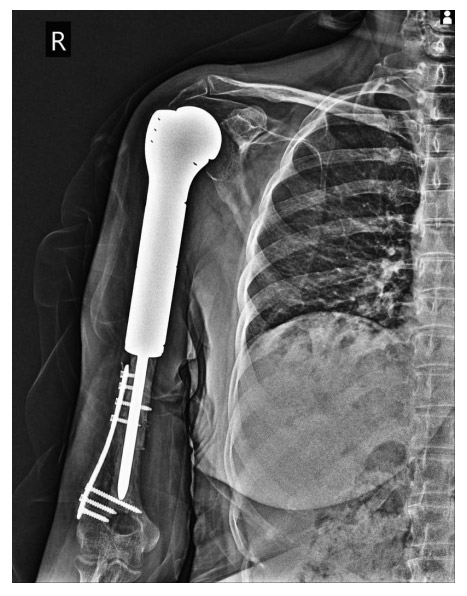

Ameliyat Sonrası: Röntgende rezeksiyon sonrası distalde geri kazanılan kemiğin anatomik plak ile fiksasyonu ve çimentolu proksimal humerus tümör protezi uygulanımı görülmekte